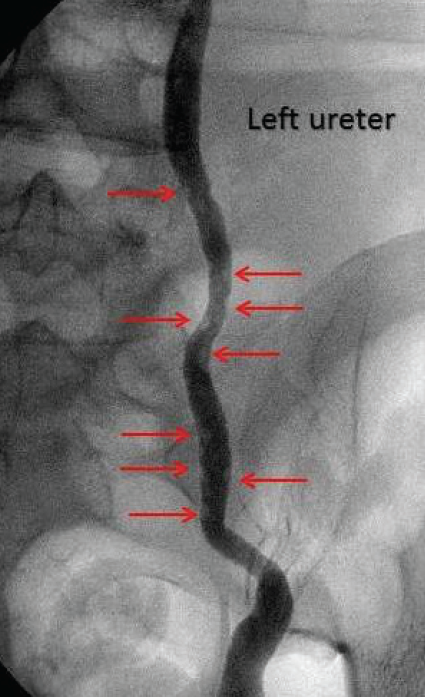

Zachary M. Zwolak, DO; Robert C. Langan, MD

A 20-year-old, gravida 3, para 3 woman presented to the ED 11 days postpartum with right lower quadrant abdominal pain that had...